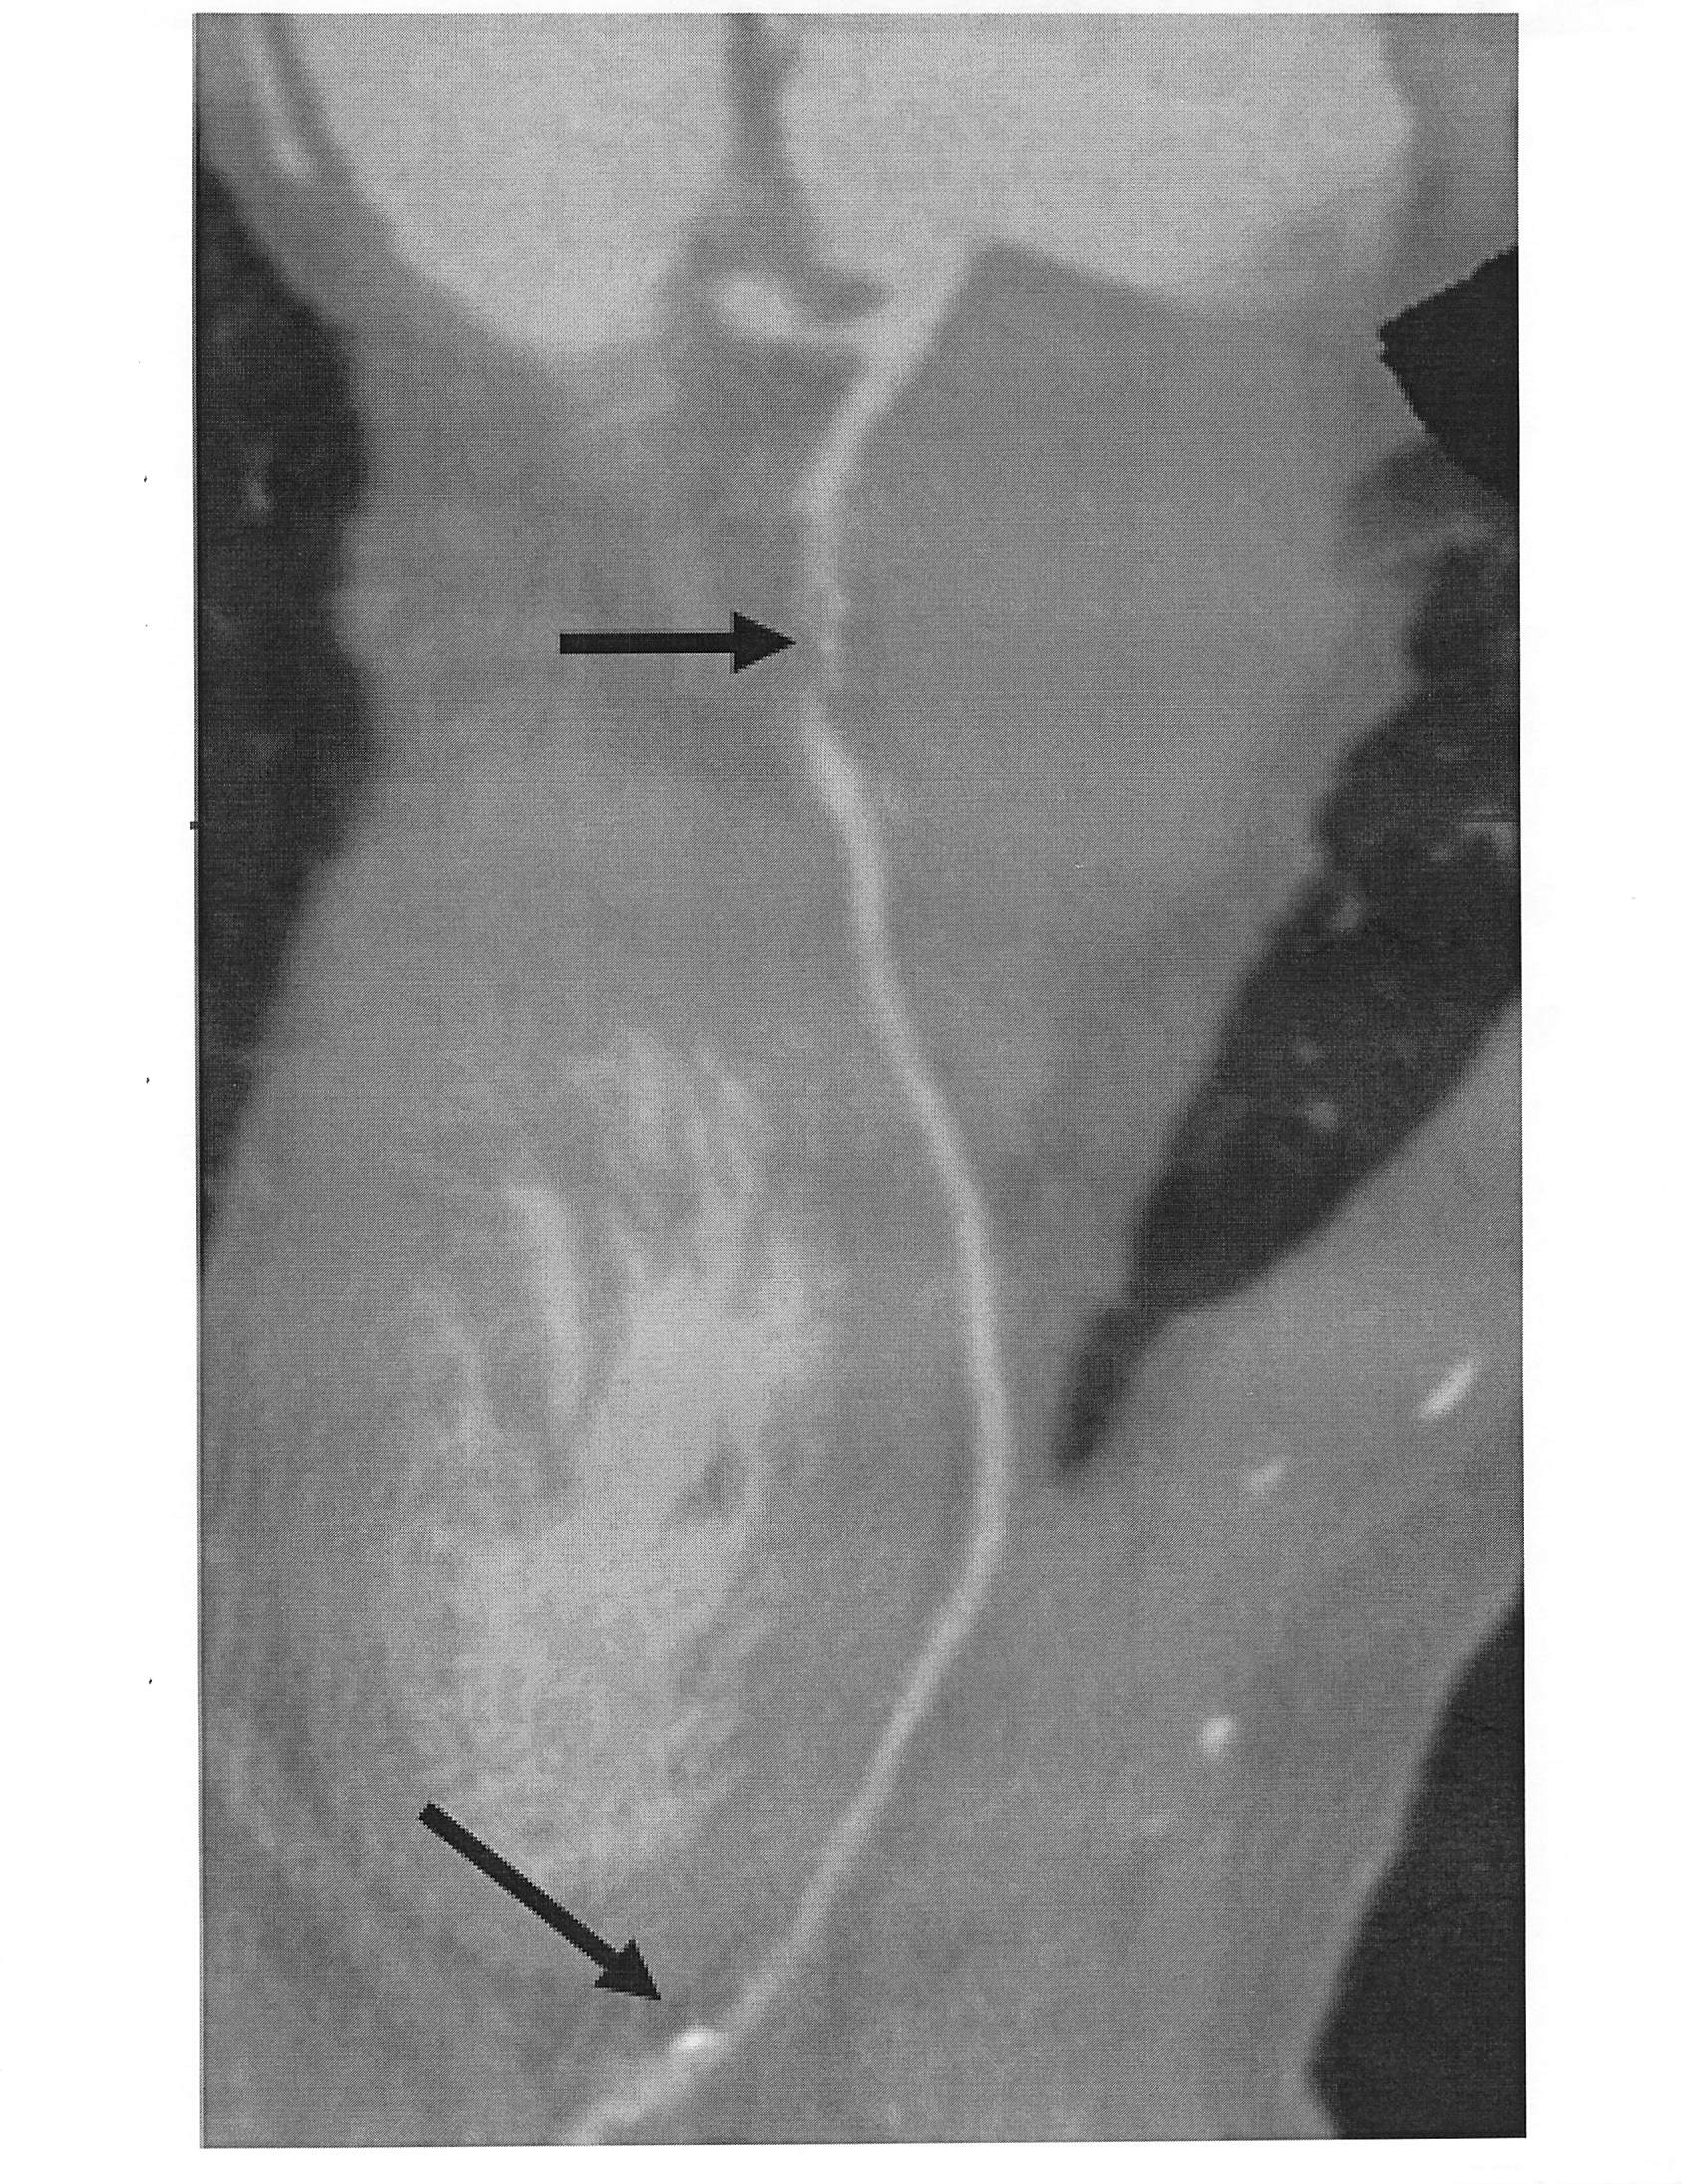

Right Photos are my arteries and are links, yikes! What does artery disease look like on a CTA? A 2017 CTA photo of my arteries: The left photo unfortunately shows the current disease in the CFX artery. My recent radiological report from these photos mentions coronary artery disease only and depicts the stenosis within the artery as a percentage, mine is < 25% great, but this is only a guesstimate and can vary 10% 20% and up to 30% is my understanding. I have seen two cardiologists since with the radiological report and they both say great less than 25%, blockage while neither actually even bothered to look at the photo with the actually disease. I asked both doc's if they would like to see the photos and they both declined. The Stenosis reported in the above angio photo group (BEFORE / AFTER) at the time of the stent was reported as 40% 50% and 60% by angio cath and now by CTA they say < 25%, I am in the process of finding out by comparison if this is true, I will be comparing the 2013 CTA to the 2017 CTA. By observation I noticed the overall sublumenal disease show in photos has not seemed to change much if at all. I also learned that the angio photo guesstimates are just that and do not hold much weight as far a accuracy if at all, they appear to be visual guides with numbers attached by the surgeon and or helper at the time of the CATH, why bother except to sell more operations. So in 2013 my artery blockages were 40-50-60% determined by the angiogram now compared to a CTA they are less than 25%, yea right, wishful thinking for sure. The disease looks the same to me photos to be posted. Can't help thinking that they do many unnecessary by pass operations based on the CATH readings/photos which are at best only guesstimates in most cases. i.e. I recently had a friend diagnosed by CATH that he had 80% blockages is all four arteries and received an immediate quadruple by bass operation? When you go under you basically give them cart blanche to do what is necessary, the way I got around this was to get the CTA before the CATH, In my case I was pretty sure what was going to happen before the CATH.

In the above left photo white is calcified plaque, dark irregularities and raised areas are the disease itself . Of note: although the stenosis, narrowing is only 25% this give or take 10% -30%, yes. in most cases it is reported that the stable white plaque is not the soft vulnerable plaque that causes a heart attacks but instead its the dark areas of soft vulnerable plaque beneath the artery walls that tend to be the culprits, however they actually can occur anywhere at anytime. The idea is that through (positive remodeling) the plaque builds up pressure beneath the artery wall and finally when enough pressure or disease happens within, the area is subject to rupture. If the artery blockage us severe enough a heart attack can ensue. So passing all your basic yearly tests really don't mean a thing buddy, imaging is key! |

2013, CTA of my CFX |

2015 MRA of my CFX artery MRI machine |

2017, 640 CTA slice machine of my CFX artery Dr. Amar Shah location of Northwell CTA |

2020 curved multi planar images showing stent in LAD(left) and disease in LCX tks Dr. Shaw for great images, end view of arteries are seen on right. |